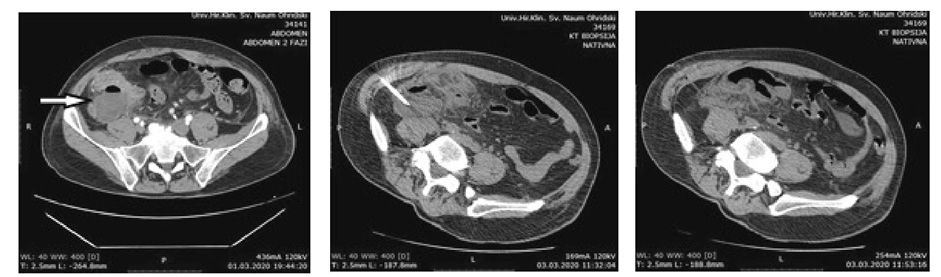

Two patients presented with postoperative pyrexia without the need of any additional intervention. There were no cases of wound infection. One patient was reoperated for early postoperative mechanical bowel obstruction and had uneventful postoperative period. One patient presented with postoperative IAA and it was successfully evacuated and drained by CT guidance (Figure 1).

Figure 1. IAA evacuation and drainage

Intraabdominal abscess occurrence is a serious postoperative complication that requires adequate treatment (sometimes a surgical one). Different series show heterogeneous data about its rate when compared between LA and OA [12, 16, 25–28]. Certain attempts are made in order to reduce its incidence such as reduction of the pneumoperitoneum pressure (low intraabdominal pressure) for eventual positive impact on bacterial translocation in the bloodstream [29, 30]. Further, pus collection suction with complete adhesiolysis and generous intraabdominal lavage with multiple drains are proposed [28]. Other authors suggest that intraabdominal lavage rises the incidence of IAA so they recommend only pus collection suction [12, 31, 32]. A third party series showed no difference between irrigation and suction versus suction alone that affects the IAA formation [33–35]. In our study, we used generous irrigation and suction and also a mandatory adhesiolysis. Intraabdominal drainage was used always in cases of diffuse peritonitis and periapendicular abscess, while in the rest of the cases, the indication for drainage was relative. There was one case of IAA in the LA group, which was statistically with no significance.

The IAA treatment can be operative (laparotomy) or with US or CT-guided percutaneous drainage. The minimal invasiveness of the procedure, its efficiency (over 90% successfulness) and no need for general anesthesia, makes the percutaneous drainage first choice method for post appendectomy IAA. However, it has some limitations when a diffuse interintestinal collections are present [36–38].